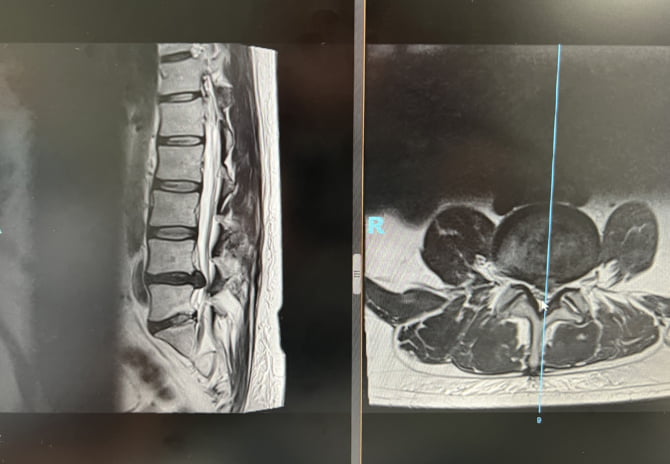

Do I STILL need surgery on my back? How the NHS has failed me

It’s very nearly a year since I had the surgery on my spine – it’s [...]